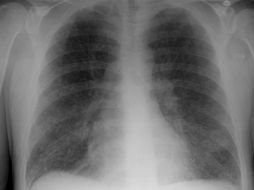

Tecnología Radiografías de tórax para detectar cáncer no salvan vidas 26 de octubre de 2011 - 12:22 hs Estudios científicos Ciencia médica

Tecnología El cáncer de pulmón, uno de los más difíciles de combatir 17 de octubre de 2009 - 15:29 hs Investigación científica Ciencia médica